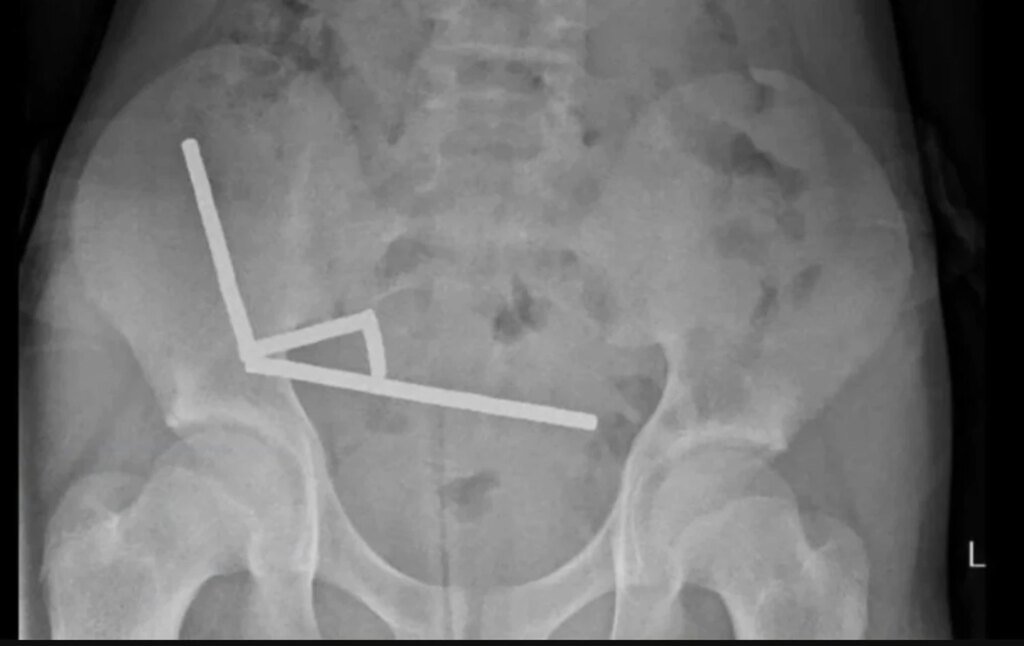

Инцидент произошел на Северном острове, в городе Тауранга. Через четыре дня сильной боли мальчика госпитализировали. Хирурги больницы извлекли магниты вместе с частями поврежденного кишечника. После восьми дней лечения ребенка выписали, сообщил New Zealand Medical Journal.

По данным врачей, подросток проглотил около 80–100 магнитов размером 5×2 мм, предположительно, "играя или из любопытства". Такие магниты запрещены к продаже в Новой Зеландии с 2013 года, однако их до сих пор можно приобрести на онлайн-площадках, несмотря на предупреждения правительства об опасности.